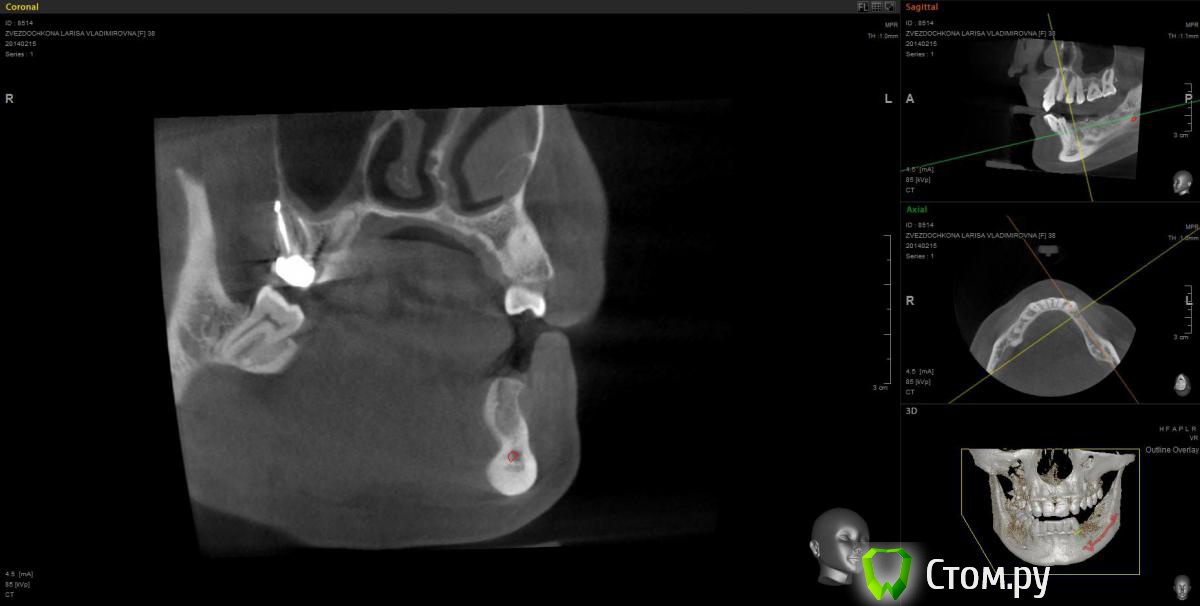

mapmax Опубликовано 3 марта, 2014 Поделиться Опубликовано 3 марта, 2014 Итак,коллеги,нуждаюсь в Вашем совете. У пациентки концевой дефект в обл 34 35 36 37, в периапикальной обл. 34 был воспалительный процесс который обострился и осенью прошлого года зуб был удален(не мной). Сейчас стоим перед имплантацией. Я рекомендую ставить импланты в обл отсутствующих зубов,но по финансовым соображениям пациентка настаивает на операции в обл 34 35 и позже в обл 36 37. Система выбрана Штрауманн SP SLActiv. Из за особенностей формы альвеолярного отростка в обл. 34 35( S-образная) и недавнего удаления 34 я рассматриваю установку импланта с язычным наклоном размера 4.8х10 RN в обл 35 RN 4.8х12. Но есть опасность оголения витков с вестибулярной стороны.Может все же сперва провести аугментацию "Аллопластом" с мембраной с вестибулярной стороны и отсрочено имплантация?! Срезы ДКТ прилагаю. Спасибо. Ссылка на комментарий

mapmax Опубликовано 5 марта, 2014 Автор Поделиться Опубликовано 5 марта, 2014 тоже склоняюсь к этому варианту.Тем более я чувствую в обл 3.4 киста, уж больно плотность костной ткани в этой обл.сомнительная. Ссылка на комментарий